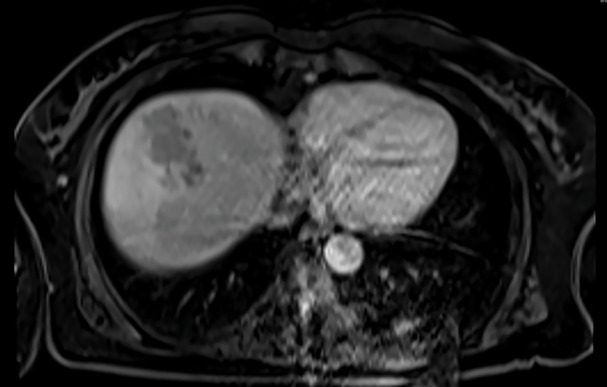

A 57-year-old female patient presented with fever, nausea, vomiting, loss of appetite, and weight loss within the last two months. Ceftriaxone and metronidazole therapy was started upon discovery of a liver abscess but provided no benefit. Following the of abscess biopsy, the patient developed fever, itching, anemia, acute renal failure, hyperbilirubinemia, and eosinophilia that required intensive care unit (ICU) admission. The Fasciola hepatica antibodies were detected by enzyme-linked immunosorbent assay (ELISA). Triclabendazole was started, after which the symptoms and magnetic resonance imaging (MRI) findings regressed. Even without eosinophilia, F. hepatica should be considered in cases with a liver abscess that does not respond to antibiotics.

Abstract Image